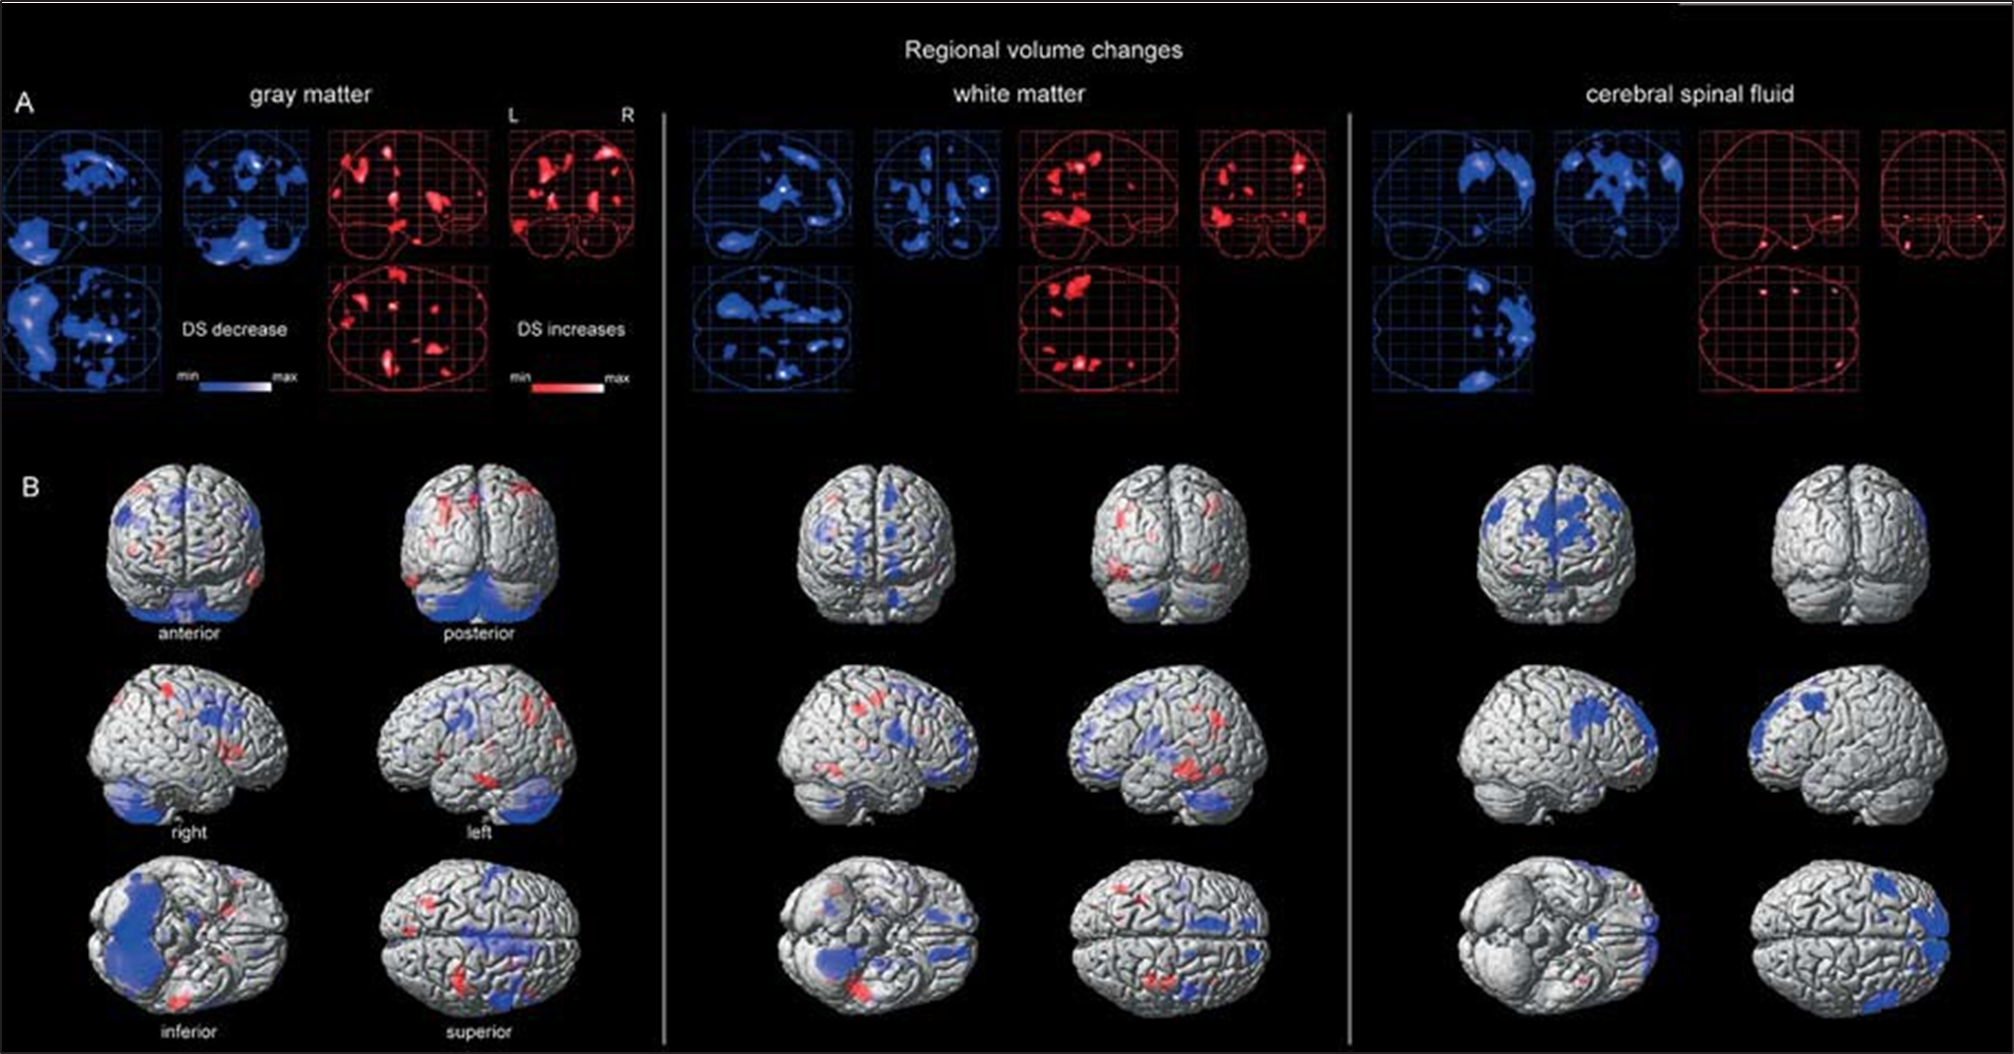

Studio di Morfometria Voxel-Based dell’Intero Cervello in Bambini e Adolescenti con Sindrome di Down – Copy

Lo studio con risonanza magnetica ad alta risoluzione rivela nei giovani con sindrome di Down una riduzione diffusa della sostanza grigia e bianca, soprattutto nel cervelletto e nei lobi frontali, confermando alterazioni strutturali già in età evolutiva